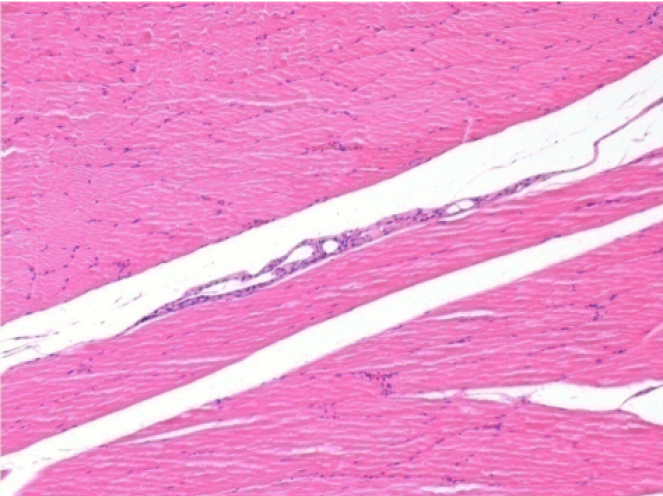

1 month after Endopeel Injection 0.1ml in the right pretibial muscle.

What is seen in black on the pictures is not a necrosis like could imagine some scientifics !

In fact, 4 conclusions have to be taken in consideration